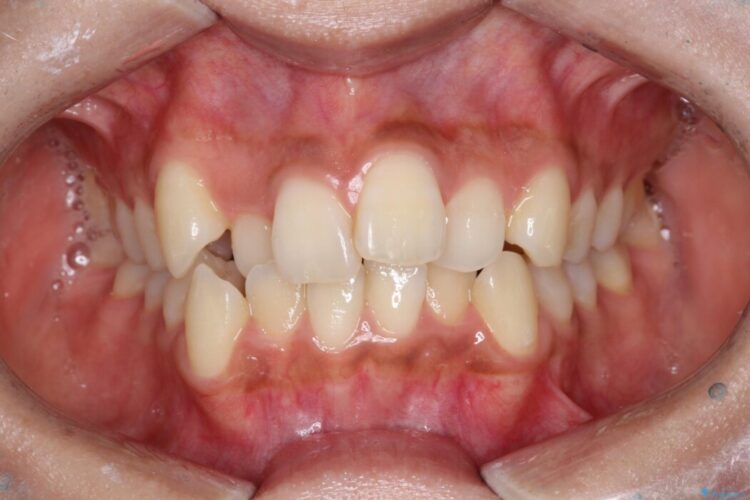

前歯のガタつきと、口元の突出感を改善したいと来院されました。

矯正検査の結果、歯を並べるスペースが不足しており、そのまま並べてしまうとさらに突出感が目立つ恐れがありました。

そのため上下左右4番を抜歯し、ガタつきを改善しながら前歯をしっかりと後方へ下げ、口元のボリュームを抑えていく計画を立案しました。

複雑に重なり合っていた前歯を、抜歯で作ったスペースを活用して丁寧に整列。単に並べるだけでなく、角度を1ミリ単位で調整しながら後ろへ下げることで、口元の突出感をスッキリ解消しました。

理想のEラインと、ガタつきのない美しい歯並びを同時に手に入れられました。